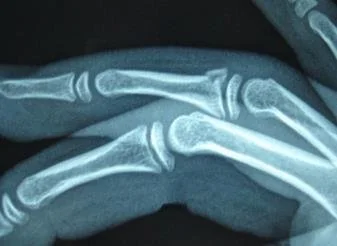

Arthritis Children Congenital Trigger Thumb Childrens Hand Fractures Childrens Wrist Fractures Ganglions Finger Tip Injuries Seymour Fracture